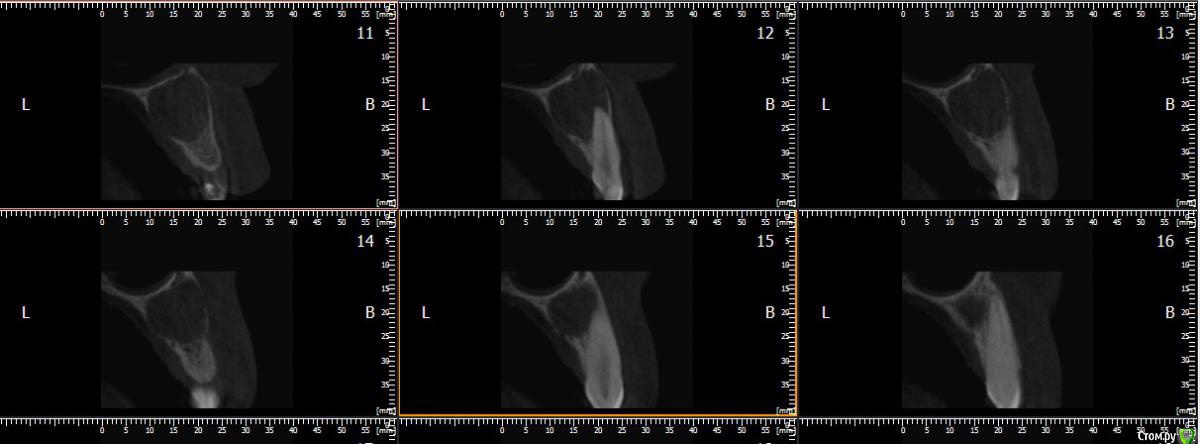

Рустам Опубликовано 17 января, 2016 Поделиться Опубликовано 17 января, 2016 Добрый вечер коллеги! Обратилась пациентка с жалобами на наличие свища в области 22 зуба. Сделали КТ, обширный очаг в области 21, 22. Как считаете, можно попытаться в данной ситуации обойтись консервативным лечением, без хирургии? Ссылка на комментарий